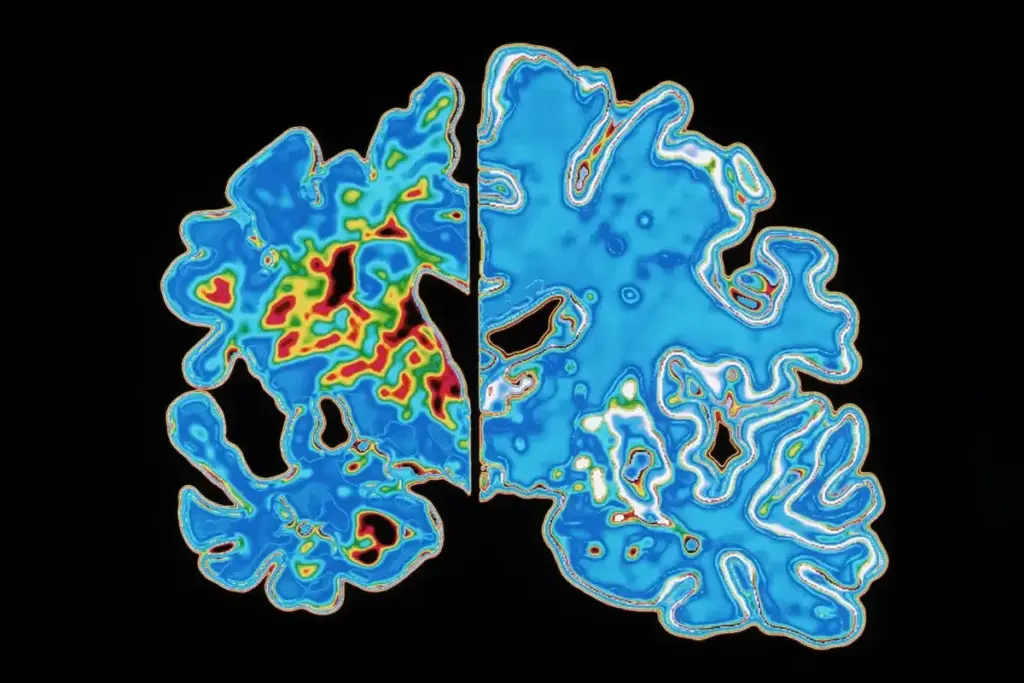

Dementia is a broad term for brain conditions, but senile brain degeneration means actual tissue loss. Knowing what is senile degeneration of the brain helps families get help early. This slow degeneration of brain tissue gives a chance for special support.

Senile degeneration of the brain is complex, involving many changes. As we get older, our brains naturally change, affecting how we think. But, senile degeneration is a deeper decline in thinking skills, greatly impacting our life quality.

Senile brain degeneration means a drop in thinking skills, like memory loss and problem-solving issues. It’s linked to aging but isn’t just a normal part of growing older. In medical terms, it’s often confused with dementia, but it’s more about brain changes.

In the past, “senile degeneration” was used to describe cognitive decline in older adults. But today, medicine uses more precise terms. Dementia is now seen as a syndrome caused by different diseases, with Alzheimer’s being the most common.

The change in medical terms shows a better understanding of these conditions. Today, doctors use specific criteria to diagnose different types of cognitive impairment.